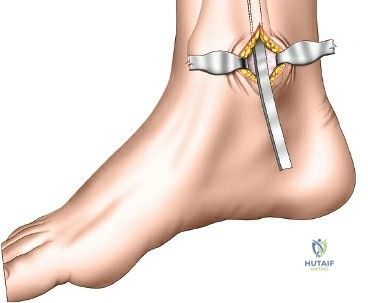

Plate Insertion & Fixation

- Plate Selection: Precontoured, anatomically shaped distal tibia locking plates are the standard. They are designed to fit the specific contours of the distal tibia and feature multi-directional locking screw options distally. The plate length should be adequate to span the fracture zone, providing sufficient working length (distance between screws nearest to the fracture) to allow for relative stability in metaphyseal fractures.

- Plate Insertion:

- The chosen plate is carefully slid into the submuscular/subcutaneous tunnel created earlier, from either the proximal or distal incision.

- A plate inserter handle or targeting guide may be used to maneuver the plate and align it correctly on the bone surface.

- Confirm plate position with fluoroscopy (AP and lateral views), ensuring it is centered on the bone and its distal extent is appropriate relative to the joint line.

- The plate should ideally rest directly on the bone, minimizing soft tissue tension.

- Temporary Fixation: Once the plate is positioned, it can be temporarily secured to the bone using K-wires or a plate-holding clamp through designated holes. This allows for final adjustments before permanent screw insertion.

- Screw Placement:

- Distal Locking Screws: These screws are inserted first to secure the plate to the distal fragment(s). Using the plate's targeting guide, drill guides are utilized to ensure accurate placement of locking screws. Fluoroscopy is critical to confirm that screws are not entering the ankle joint. Typically, 3-4 divergent locking screws are placed in the distal fragment to maximize pullout strength and angular stability.

- Proximal Screws: Proximal locking screws are then inserted into the tibial diaphysis. The number and type (locking vs. non-locking cortical) depend on the fracture pattern and bone quality. For metaphyseal fractures, often 3-4 locking screws are sufficient proximally to provide adequate stability.

- Lag Screws (Optional): If a large, reconstructible primary fracture fragment is present, a percutaneous lag screw can be inserted prior to plate application to achieve absolute stability of that fragment, followed by plate application for neutralization and additional support.

- Joint Penetration Check: After each distal screw, fluoroscopic images (AP, lateral, and true mortise views, possibly oblique views) are meticulously checked to ensure no intra-articular penetration. Articular cartilage violation can lead to significant post-traumatic arthritis.

- Final Assessment: After all screws are inserted, the reduction, alignment, and rotation are re-confirmed with multiple fluoroscopic views. The implant should be well-seated, and the soft tissues should not be under excessive tension.